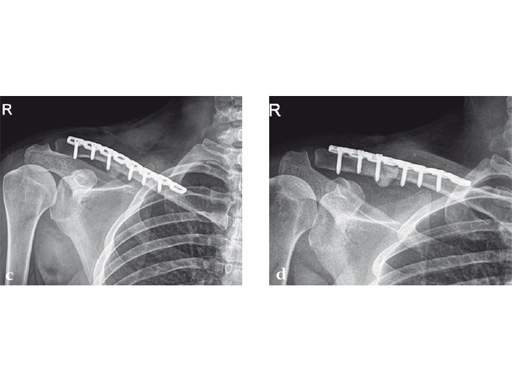

Case 2: a 29-year-old man sustained a midshaft clavicle fracture while playing soccer.

Case provided by Norbert Sdkamp and Martin Jaeger, Freiburg, Germany